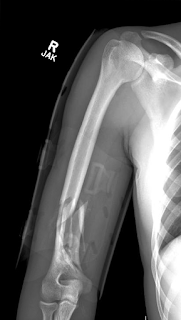

Below there is an example of failure of the repaired subscapularis which was was found during surgery to be only stretching of the upper 2/3 of the row border of the tendon. For that reason it was easy to repair it back to the bone. Axillary xray indicates the rupture below.

This axillary view indicates anterior subluxation, failure of subscapularis